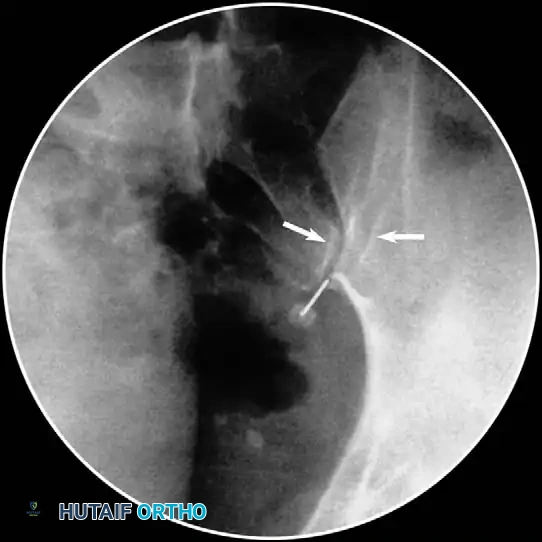

- Epidurogram Confirmation: Inject the contrast under live fluoroscopy to produce an epidurogram. Adjust the C-arm to a lateral perspective to definitively document posterior epidural spread and rule out intrathecal or intravascular flow.

- Foraminal Entry: Redirect the needle to "walk off" the bone into the posterior foramen by 3 to 4 mm. Do not advance further medially than the midpoint of the articular pillar on the AP view.

- Contrast Flow: Remove the stylet. Aspirate vigorously. Inject 0.5 mL of nonionic contrast under live fluoroscopy. You must observe filling of the oval neuroforamen and distal flow along the exiting nerve root. If rapid vascular washout is seen, abort the procedure immediately.

- Contrast Injection: Live fluoroscopy during contrast injection must demonstrate medial flow into the epidural space and lateral flow outlining the exiting spinal nerve.

Clinical Pearl: The absence of epidural flow during a lumbar transforaminal injection often indicates severe foraminal stenosis or perineural fibrosis. In these cases, the diagnostic value is high, confirming that the nerve root is mechanically tethered and likely requires surgical decompression.